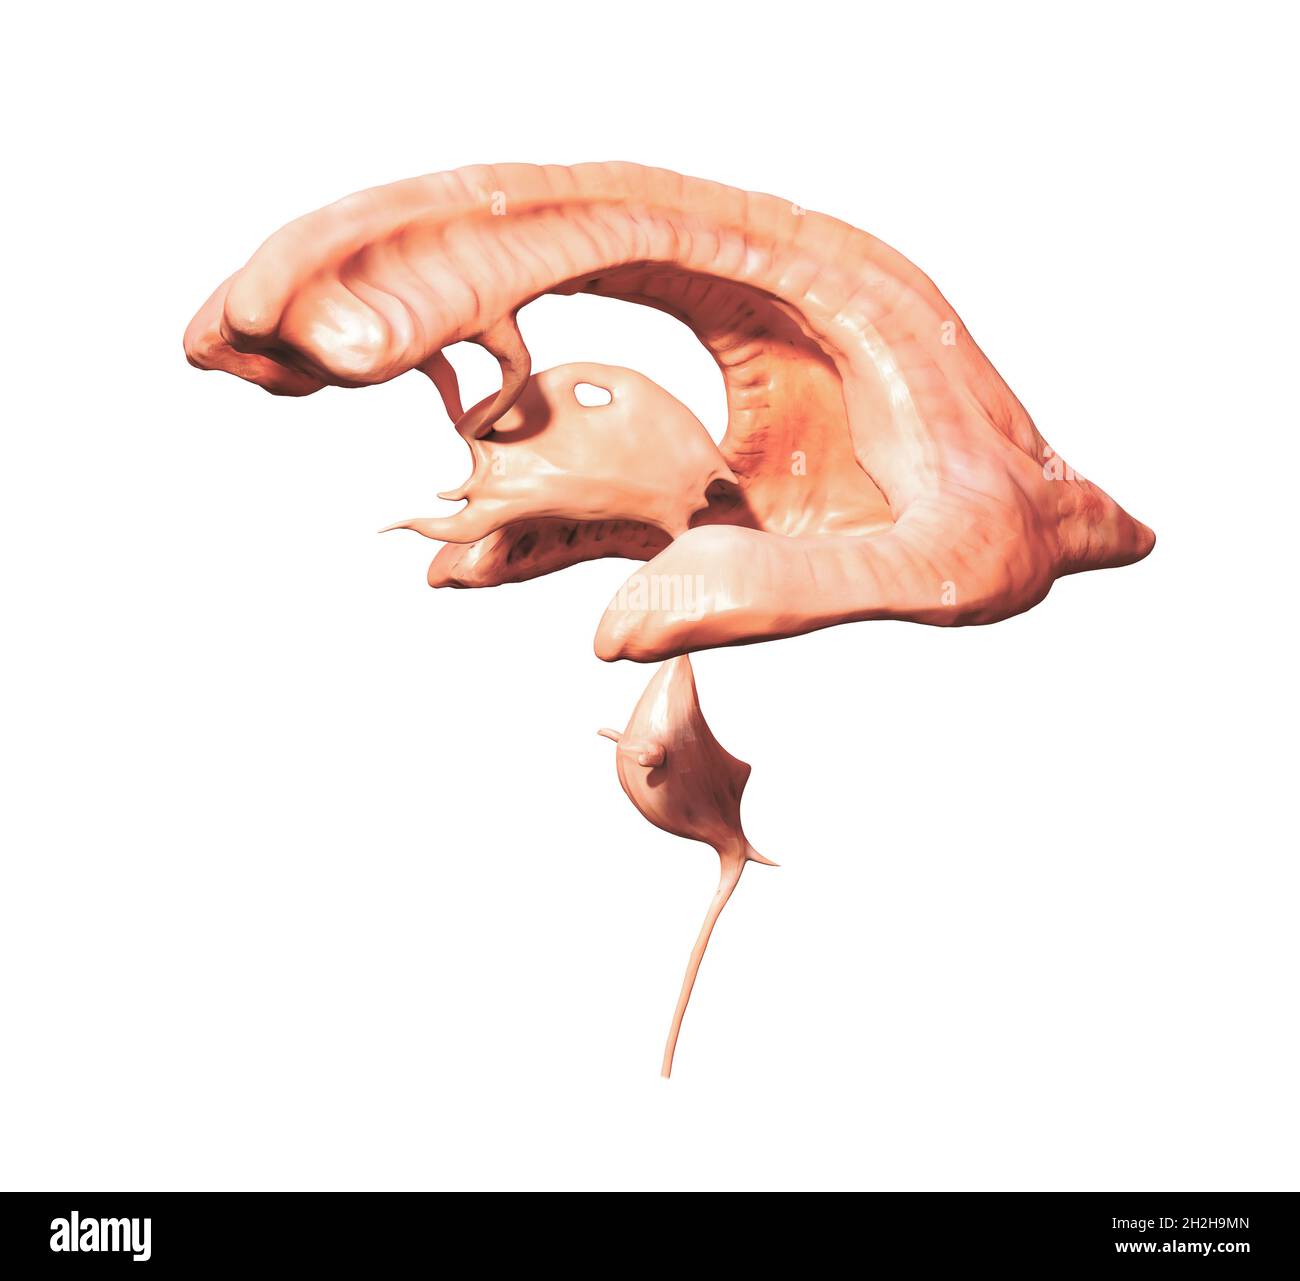

RM2AWF8JC–Die Anatomie des Nervensystems, vom Standpunkt der Entwicklung und Funktion. -Ant. HornCentra, Teil Latcral vnnInf. Horn Q virale Pari Ant. Horn. Ventrikel Ventrikel Ventrikel Ventrikel Ventrikel Ventrikel Ventrikel Ventrikel Ventrikel Ventrikel Ventrikel Ventrikel Ventrikel Ventrikel Ventrikel Ventrikel Ventrikel Ventrikel Ventrikel Ventrikel ^^ 176.-Zwei Ansichten der Hirnventrikel des Menschen: A, Dorsale Ansicht; B, laterale Ansicht. Das Vorderhorn oder Cornu anterius ist der Teil, der rostral zum interventrikulären Foramen liegt. Seine Dach- und Rostrallgrenze wird von Thecorpus callosum gebildet. Sein mediales

RM2AWFNN9–Menschliche Anatomie, einschließlich Struktur und Entwicklung und praktische Überlegungen d in einem sagittalen mesialen Abschnitt (Abb. 910) wird jede dieser Teilungen als mit einem Teil des Systems der Kommunikation von Räumen verwandt angesehen, die als die dritten Ventrikel des Lateralands, der Aquädukt von Sylvius und der vierte Ventrikel die oben genannten Gehirnhemisphären ausdehnen. Durch den Hirnstamm und unter dem Kleinhirn bis zum zentralen Kanal des Rückenmarks. Da die lateralen Ventrikel zwei innumerieren, ist die Theirstellung im Zusammenhang mit den Gehirnhemisphären, in denen sie liegen, lateral zum m

RM2AN4TWY–Handbuch der allgemeinen, beschreibenden und pathologische Anatomie (Band 2). Ventrikel, ein. Ventrikel des Kleinhirns, b. Aquädukt von Sylvius, C. Dritten Ventrikel, d. Lateralen Ventrikel, 1. Vordere Horn, 2. Hintere Horn, 3. Absteigend Horn, II. Textur, III. Gewicht, IV. Konsistenz, Kap. Iii. Umhüllt des Gehirns. Abt. Ich. Pia - mater, I. des Rückenmarks, II. Von Hirn, ein. - Externe Pia mater, b. Interne pia-mater, ich. Choroid Plexus des vierten Ventrikel, ii. Choroid Plexus des Großhirns, Art.ii.Apert-syndrom Membran, Art. hi. Dura-mater, I. spinalen Dura-mater, II. Zerebrale Dura-mater